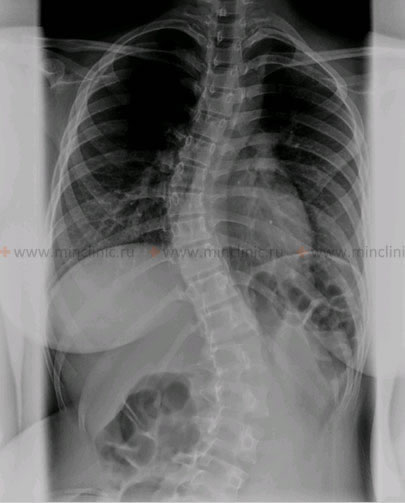

სკოლიოზის დროს გამრუდების (დეფორმაციის) ხარისხს ადგენენ ხერხემლის რენტგენოგრაფიის (პირდაპირ პროექციაში) მონაცემების მიხედვით.

ხერხემლის იდიოპათიკური სკოლიოზი რენტგენოგრაფიაზე.